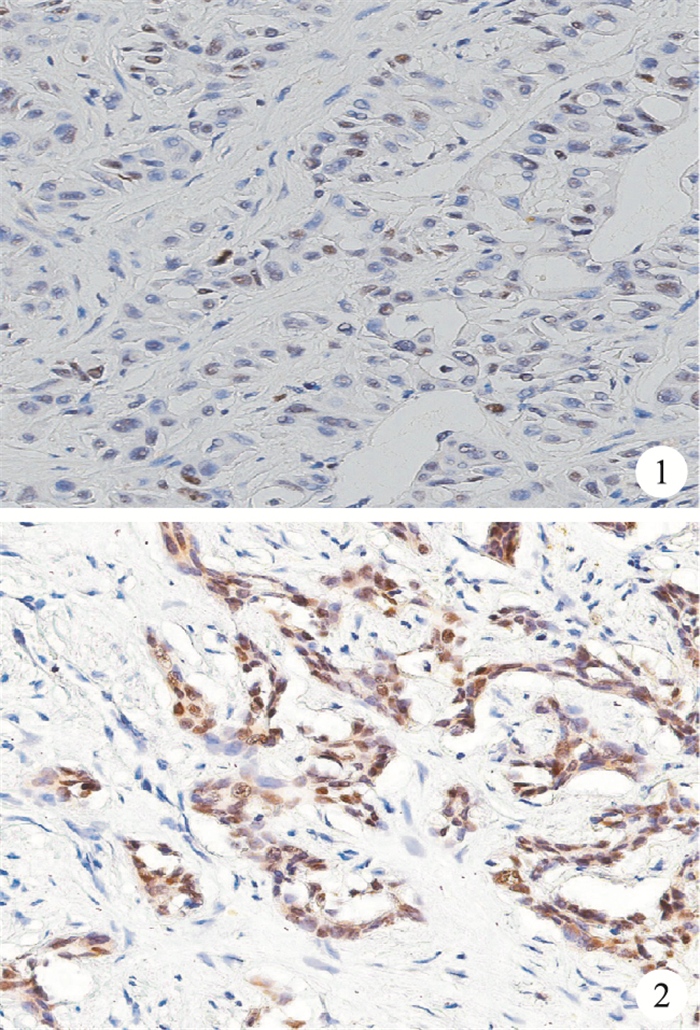

FOXA2主要表達在ICC細胞的細胞核上,以細胞核見到棕褐色染色為陽性表達。依據半定量方法對陽性表達結果進行判定,每張切片隨機選取5個高倍鏡視野以觀察細胞染色情況(取均值):陽性細胞所占比例≤50%時判定為低表達,陽性細胞所占比例 > 50%時判定為高表達。

本組ICC患者中,FOXA2呈低表達50例(圖 1),高表達35例(圖 2)。